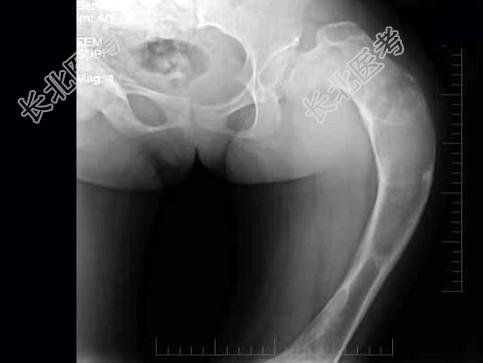

- 单项选择题女,17岁, 左髋部酸胀不适半年,骨盆正位片如图所示, 最可能的诊断是 ( )

A、骨髓炎

B、内生软骨瘤

C、骨纤维结构不良

D、骨斑点症

E、以上均不正确